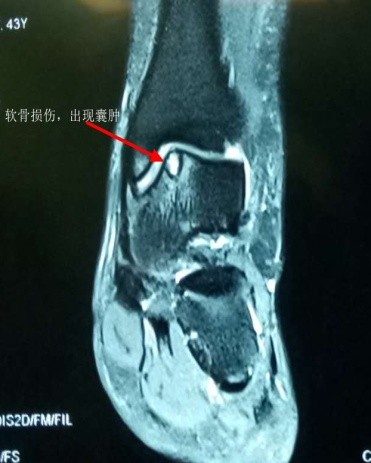

扭伤后距腓前韧带撕裂的核磁影像

慢性踝关节不稳定造成的距骨软骨损伤,形成空洞